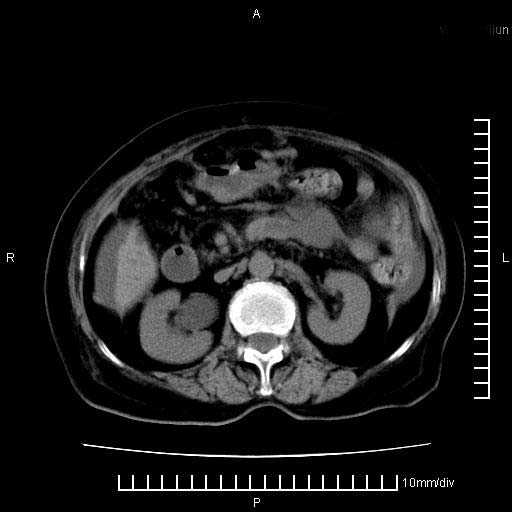

标题: CT28280:腹部增强:女性,80岁

上腹疼痛月余,外院核磁诊断胰腺癌。现临床示右下腹可明显触及包块,可片子上怎么没有看到?

4。右肾盂囊肿。

右肾盂囊肿。

3、右肾盂囊肿。

1)考虑胰腺癌并胰腺假性囊肿形成。2)肝内低密度灶,不排除转移。3)右肾盂积水。4)腹水。5)右侧胸腔积液并右肺下叶部分膨胀不全。

考虑胰腺ca伴腹膜腔转移、肝左叶转移、右肾积水。右胸腔积液。